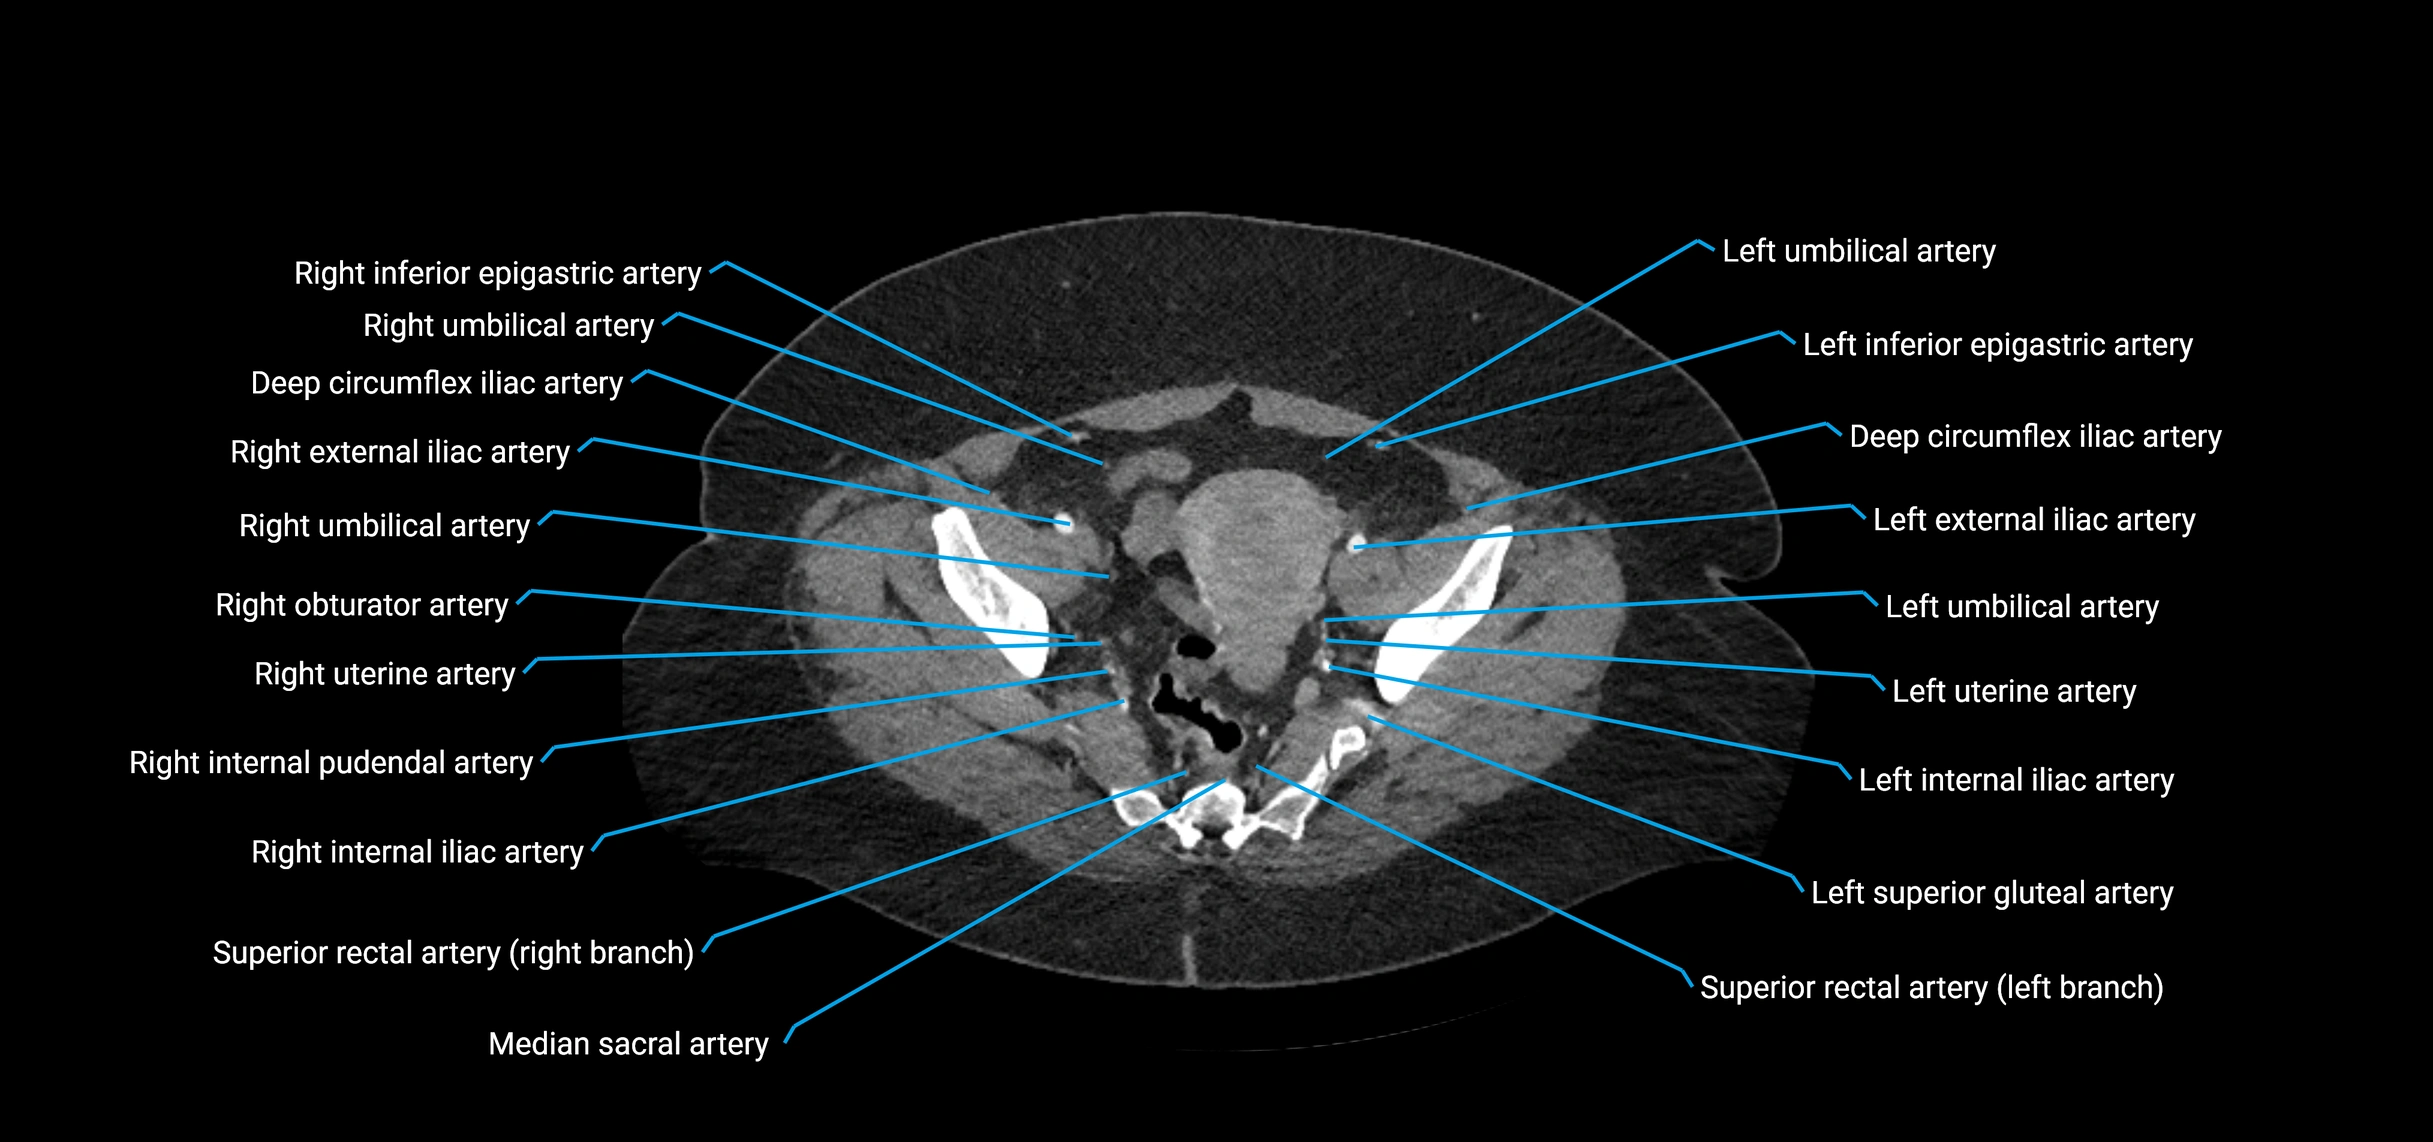

Contrast-enhanced CT (CTA):

• Gold standard for abdominal aortic imaging

• Provides excellent detail of lumen, wall, aneurysm, thrombus, and branch vessels

• Multiplanar and 3D reconstructions help in aneurysm measurement, stent graft planning, and dissection evaluation

• Detects acute rupture, traumatic injury, or occlusion with high sensitivity